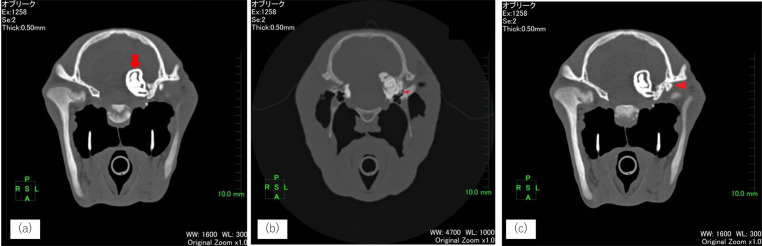

Computed tomography (CT) offers high-resolution, three-dimensional imaging, making it particularly valuable for assessing complex structures, such as the head, especially when conventional radiography and endoscopy are insufficient for a definitive diagnosis. Herein, we present two cases of equine cranial disorders resulting from congenital malformations. In case 1, which had a dentigerous cyst, CT images confirmed the location of the ectopic tooth within the skull and a detailed fistula tube. In case 2, which had temporohyoid osteoarthropathy, CT examination revealed that the stylohyoid bone was malformed, and the inner ear was presumed to be filled with soft tissue with calcification. The information obtained by CT was invaluable, as it allowed for accurate diagnosis and precise surgical planning.

计算机断层扫描(CT)提供高分辨率的三维成像,使其在评估复杂结构(如头部)时特别有价值,特别是当传统的x线摄影和内窥镜检查不足以进行明确诊断时。在此,我们提出了两个病例马颅疾病导致先天性畸形。病例1为含牙囊肿,CT图像确认了异位牙在颅骨内的位置和详细的瘘管。病例2为颞舌骨骨关节病,CT检查提示茎突舌骨畸形,推测内耳充盈有钙化软组织。CT所获得的信息是非常宝贵的,因为它允许准确的诊断和精确的手术计划。